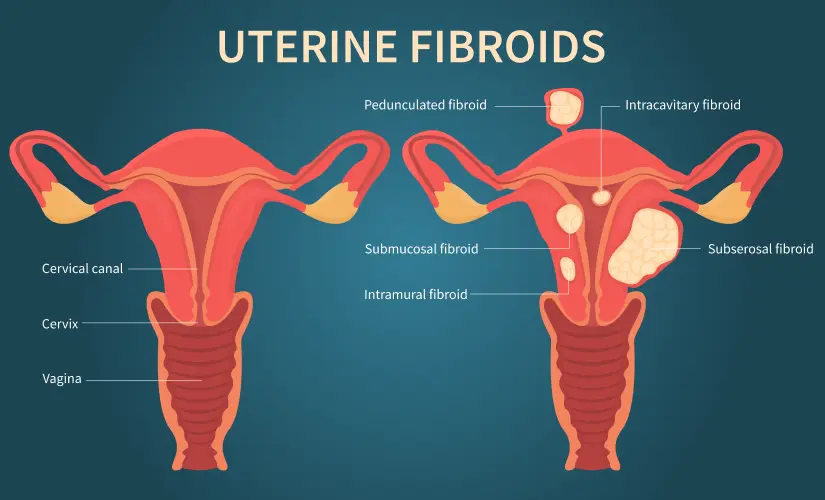

कारण 3: यूटेराइन फाइब्रॉएड – गर्भाशय में बनने वाली गांठें

यूटेराइन फाइब्रॉएड गर्भाशय में बनने वाली गैर-कैंसरयुक्त गांठें होती हैं। ये बहुत आम हैं, लेकिन कई बार बिना किसी लक्षण के भी मौजूद रह सकती हैं। जब ये गांठें गर्भाशय की दीवार को प्रभावित करती हैं, तब पीरियड्स के दौरान ब्लीडिंग बढ़ जाती है।

फाइब्रॉएड के कारण पीरियड्स लंबे हो सकते हैं, खून के बड़े-बड़े थक्के निकल सकते हैं और पेट में भारीपन महसूस हो सकता है। कुछ महिलाओं को कमर और पेट के निचले हिस्से में लगातार दर्द भी रहता है।

फाइब्रॉएड का पता आमतौर पर अल्ट्रासाउंड से चलता है, और समय पर पहचान होने पर इसका इलाज संभव है।